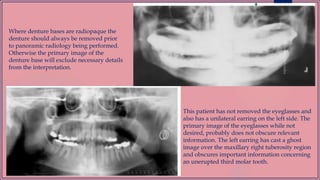

Where denture bases are radiopaque the

denture should always be removed prior

to panoramic radiology being performed.

Otherwise the primary image of the

denture base will exclude necessary details

from the interpretation.

This patient has not removed the eyeglasses and

also has a unilateral earring on the left side. The

primary image of the eyeglasses while not

desired, probably does not obscure relevant

information. The left earring has cast a ghost

image over the maxillary right tuberosity region

and obscures important information concerning

an unerupted third molar tooth.